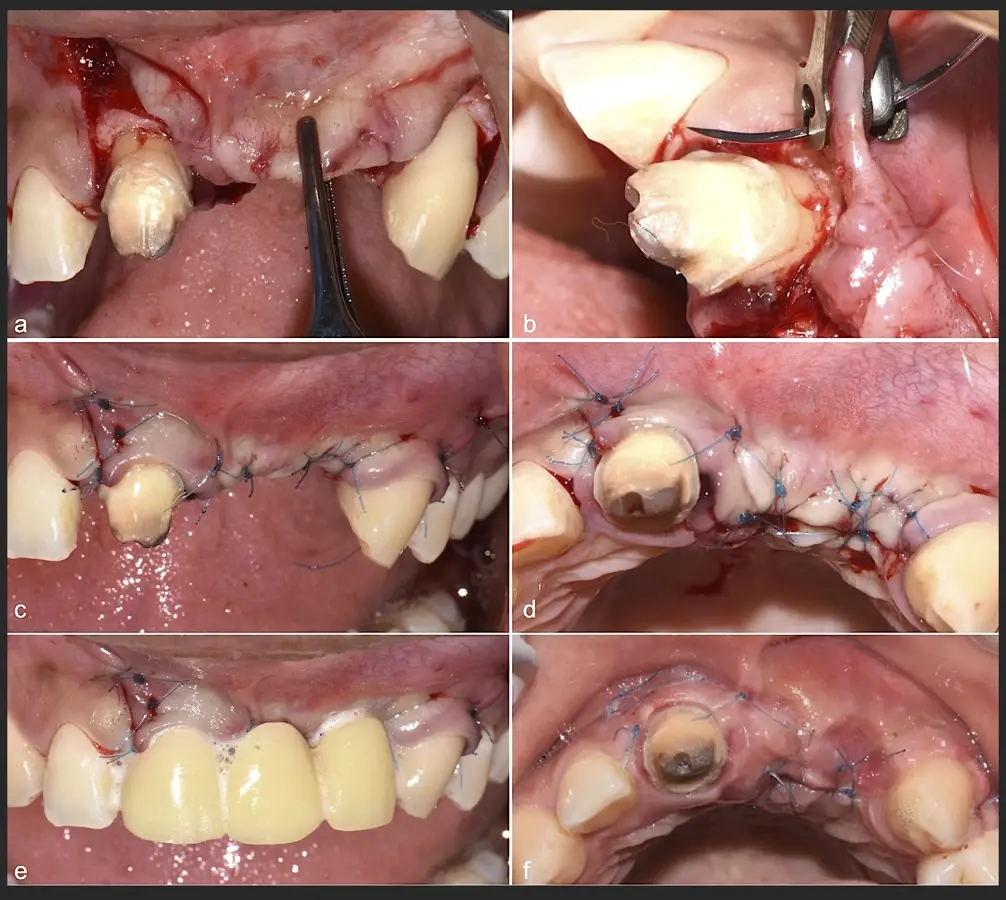

Figura 40. Secuencia de fijación y modelado del bloque óseo con inserto de corte, eliminación de ángulos agudos (a-d).

Figura 41. Modelado del bloque óseo con inserto plano de punta diamantada (a) para redondear los ángulos agudos y así evitar una dehiscencia o fenestración de los tejidos blandos (b).

Figura 44. Pasos para la colocación de la membrana de barrera (a - d).

Figura 45. Afrontamiento de colgajo y sutura (a - e). Control a los 7 días postquirúrgico (f).